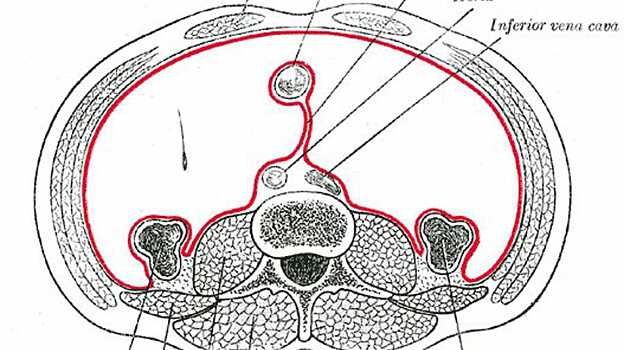

Ирландские ученые обнаружили новый орган в организме человека. Известный как брыжейка, или мезентерий, он ранее считался лишь набором фрагментированных структур в пищеварительной системе. Об открытии рассказывается на страницах журнала The Lancet: Gastroenterology and Hepatology. Ранее считалось, что кишки прикрепляются к стенкам брюшной полости посредством разрозненных тканей, однако ученые из Лимерикского университетского госпиталя пришли к выводу, что мезентерий является цельным органом, выполняющим эту функцию. Исследователи обнаружили, что мезентерий состоит из двойного сложенного слоя, «выстилающего» брюшную полость. Таким образом, его цельность и функциональность удовлетворяют критериям независимого органа. Мезентерий стал 79-м органом человеческого организма, о чем уже уведомили составителей «Анатомии Грея» — основного учебника по этому предмету в англоязычном мире.